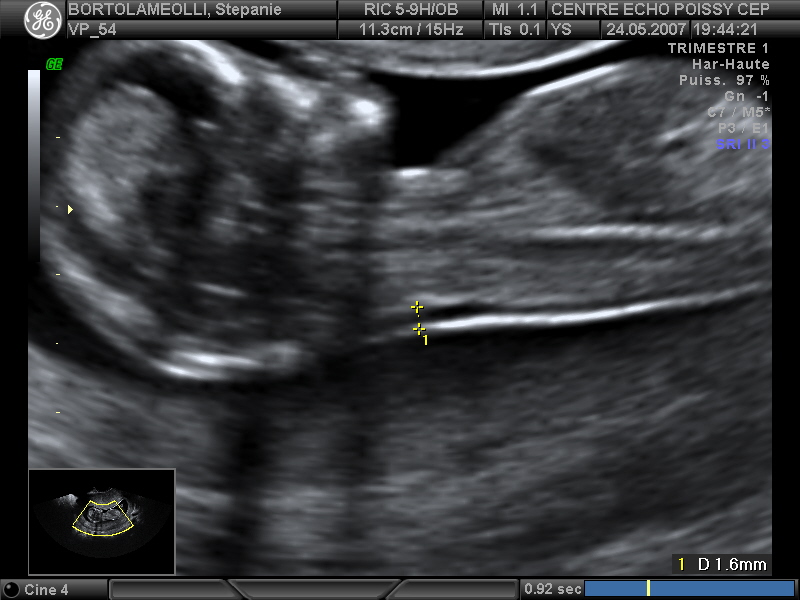

Echographies

Mai 2007